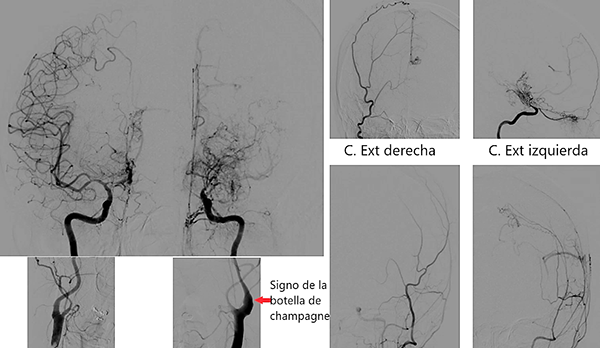

Caso clínico # 2: LD femenino de 51 años con antecedente de tabaquismo e hipertensión arterial, estudiada por deterioro cognitivo de varios meses de evolución. La RMN y ARM evidencia atrofia de hemisferio cerebral izquierdo con hiperintensidad periventricular y disminución franca del calibre de las arterias cerebral anterior y media izquierda con desarrollo de los vasos de MM (Fig. 3). La ADC muestra el stop de la arteria carótida interna izquierda distal y ausencia del origen de las cerebrales anterior y media, buen desarrollo de los vasos de MM y aporte de vasos meníngeos y etmoidales correspondiente a un grado 4 de Suzuki (Fig. 4). Se realizó una revascularización cerebral combinada: un bpTS izquierdo más EDMS y, para aumentar la perfusión en territorio de ambas arterias cerebrales anteriores, un EGPS bifrontal. En la TAC postoperatoria se evidenció un infarto fronto-polar mesial sin repercusión clínica. La ADC postoperatoria diferida evidencia una buena revascularización en los territorios de las arterias cerebral anterior y media a partir del bpTS y la doble sinangiosis (Fig. 5).

Fig. 4 Caso clínico # 2. ADC preoperatoria con compromiso bilateral de las arterias carótidas supraclinoidea mayor a izquierda, vasos de MM y presencia de anastomosis leptomeníngeas. Nótese el signo de la botella de champagne en el origen de la arteria carótida interna cervical, presente en los MM avanzados. Corresponde a un grado 4 de Suzuki